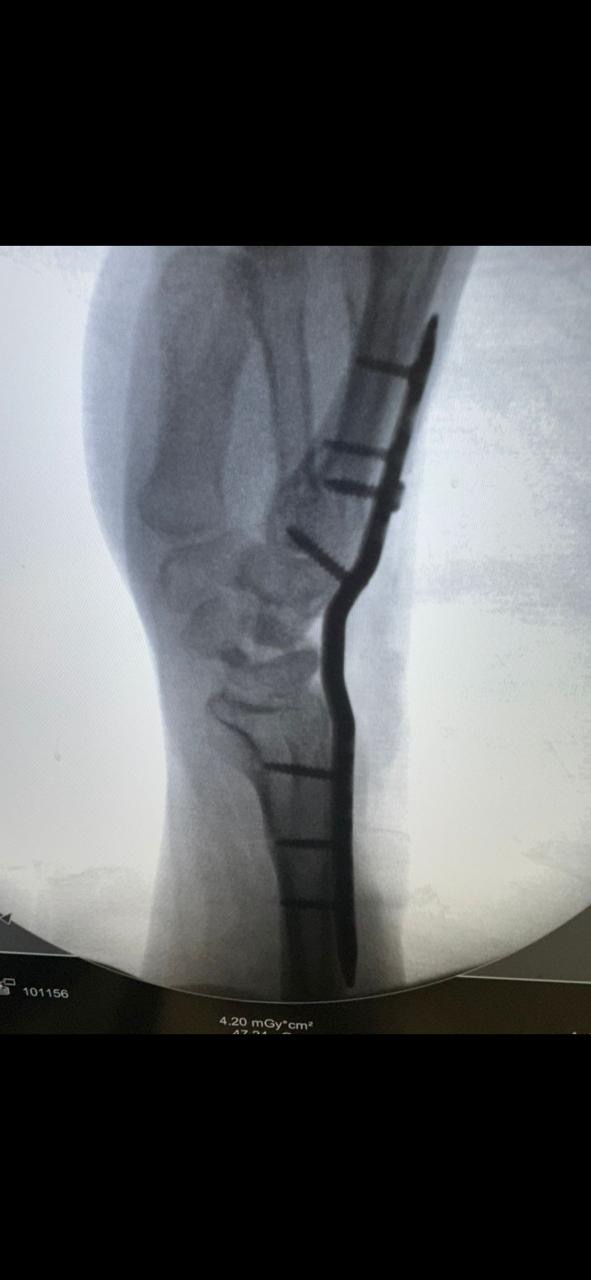

وقال فارس:“تم تحويلي لطبيب في القاهرة، وفضلت مستني من شهر 12 لسنة 2023 لحد شهر 2 لسنة 2024 عشان العملية تتعمل، وبعد أول غيار فوجئت إن العملية اتعملت جراحة مفتوحة مش منظار، رغم إن التقارير كانت بتوصي بمنظار.”

وأضاف:“لما سألت الطبيب عن سبب إجراء جراحة بدل المنظار، قالي إن الجراحة أفضل وإن إيدي هترجع أحسن من الأول، لكن بعد انتهاء فترة الجبس وخضوعي لجلسات علاج طبيعي، اكتشفت إن حالتي لم تتحسن، وإن إيدي محتاجة تدخل جراحي تاني.”

“خطأ طبي ضيّع مستقبلي.. وآخر عملية كانت تثبيت مفصل”

وأكد اللاعب أن ما حدث له هو نتيجة خطأ طبي، قائلًا:“الدكتور استسهل إجراء الجراحة بدل المنظار، وده تسبب في مضاعفات خلتني أرجع أعمل عمليات تانية، آخر عملية كانت في شهر أكتوبر اللي فات، وتم فيها تثبيت مفصل، ومع عمليات أخرى، للأسف إيدي مش هترجع زي الأول بسبب الخطأ الطبي.”